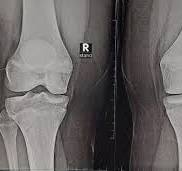

أعلن فريق بحثي في مقاطعة تشيجيانغ شرق الصين، عن ابتكار طبي جديد يتمثل في "غراء عظمي" قادر على معالجة الكسور وتركيب الشظايا العظمية خلال ثلاث دقائق فقط، في خطوة وصفت بأنها اختراق علمي في عالم جراحة العظام.

وأكدت الاختبارات المعملية أن Bone-02 نجح في تحقيق نتائج جيدة من حيث السلامة والفعالية، وفي إحدى التجارب، أجريت العملية في أقل من 180 ثانية (ثلاث دقائق)، بينما كانت طرق العلاج التقليدية تتطلب وقتا طويلا لزرع صفائح فولاذية ومسامير.

وبحسب الاختبارات المعملية، تمكن الغراء من تحقيق قوة ربط تفوق 400 رطل، وقوة قص تبلغ نحو 0.5 ميغاباسكال، وقوة ضغط تقارب 10 ميغاباسكال، كما أظهرت التجارب على أكثر من 150 مريضا نتائج ناجحة، ما يعزز احتمالية أن يصبح بديلا للزراعات المعدنية التقليدية التي تستخدم في تثبيت العظام، كما يقول العلماء